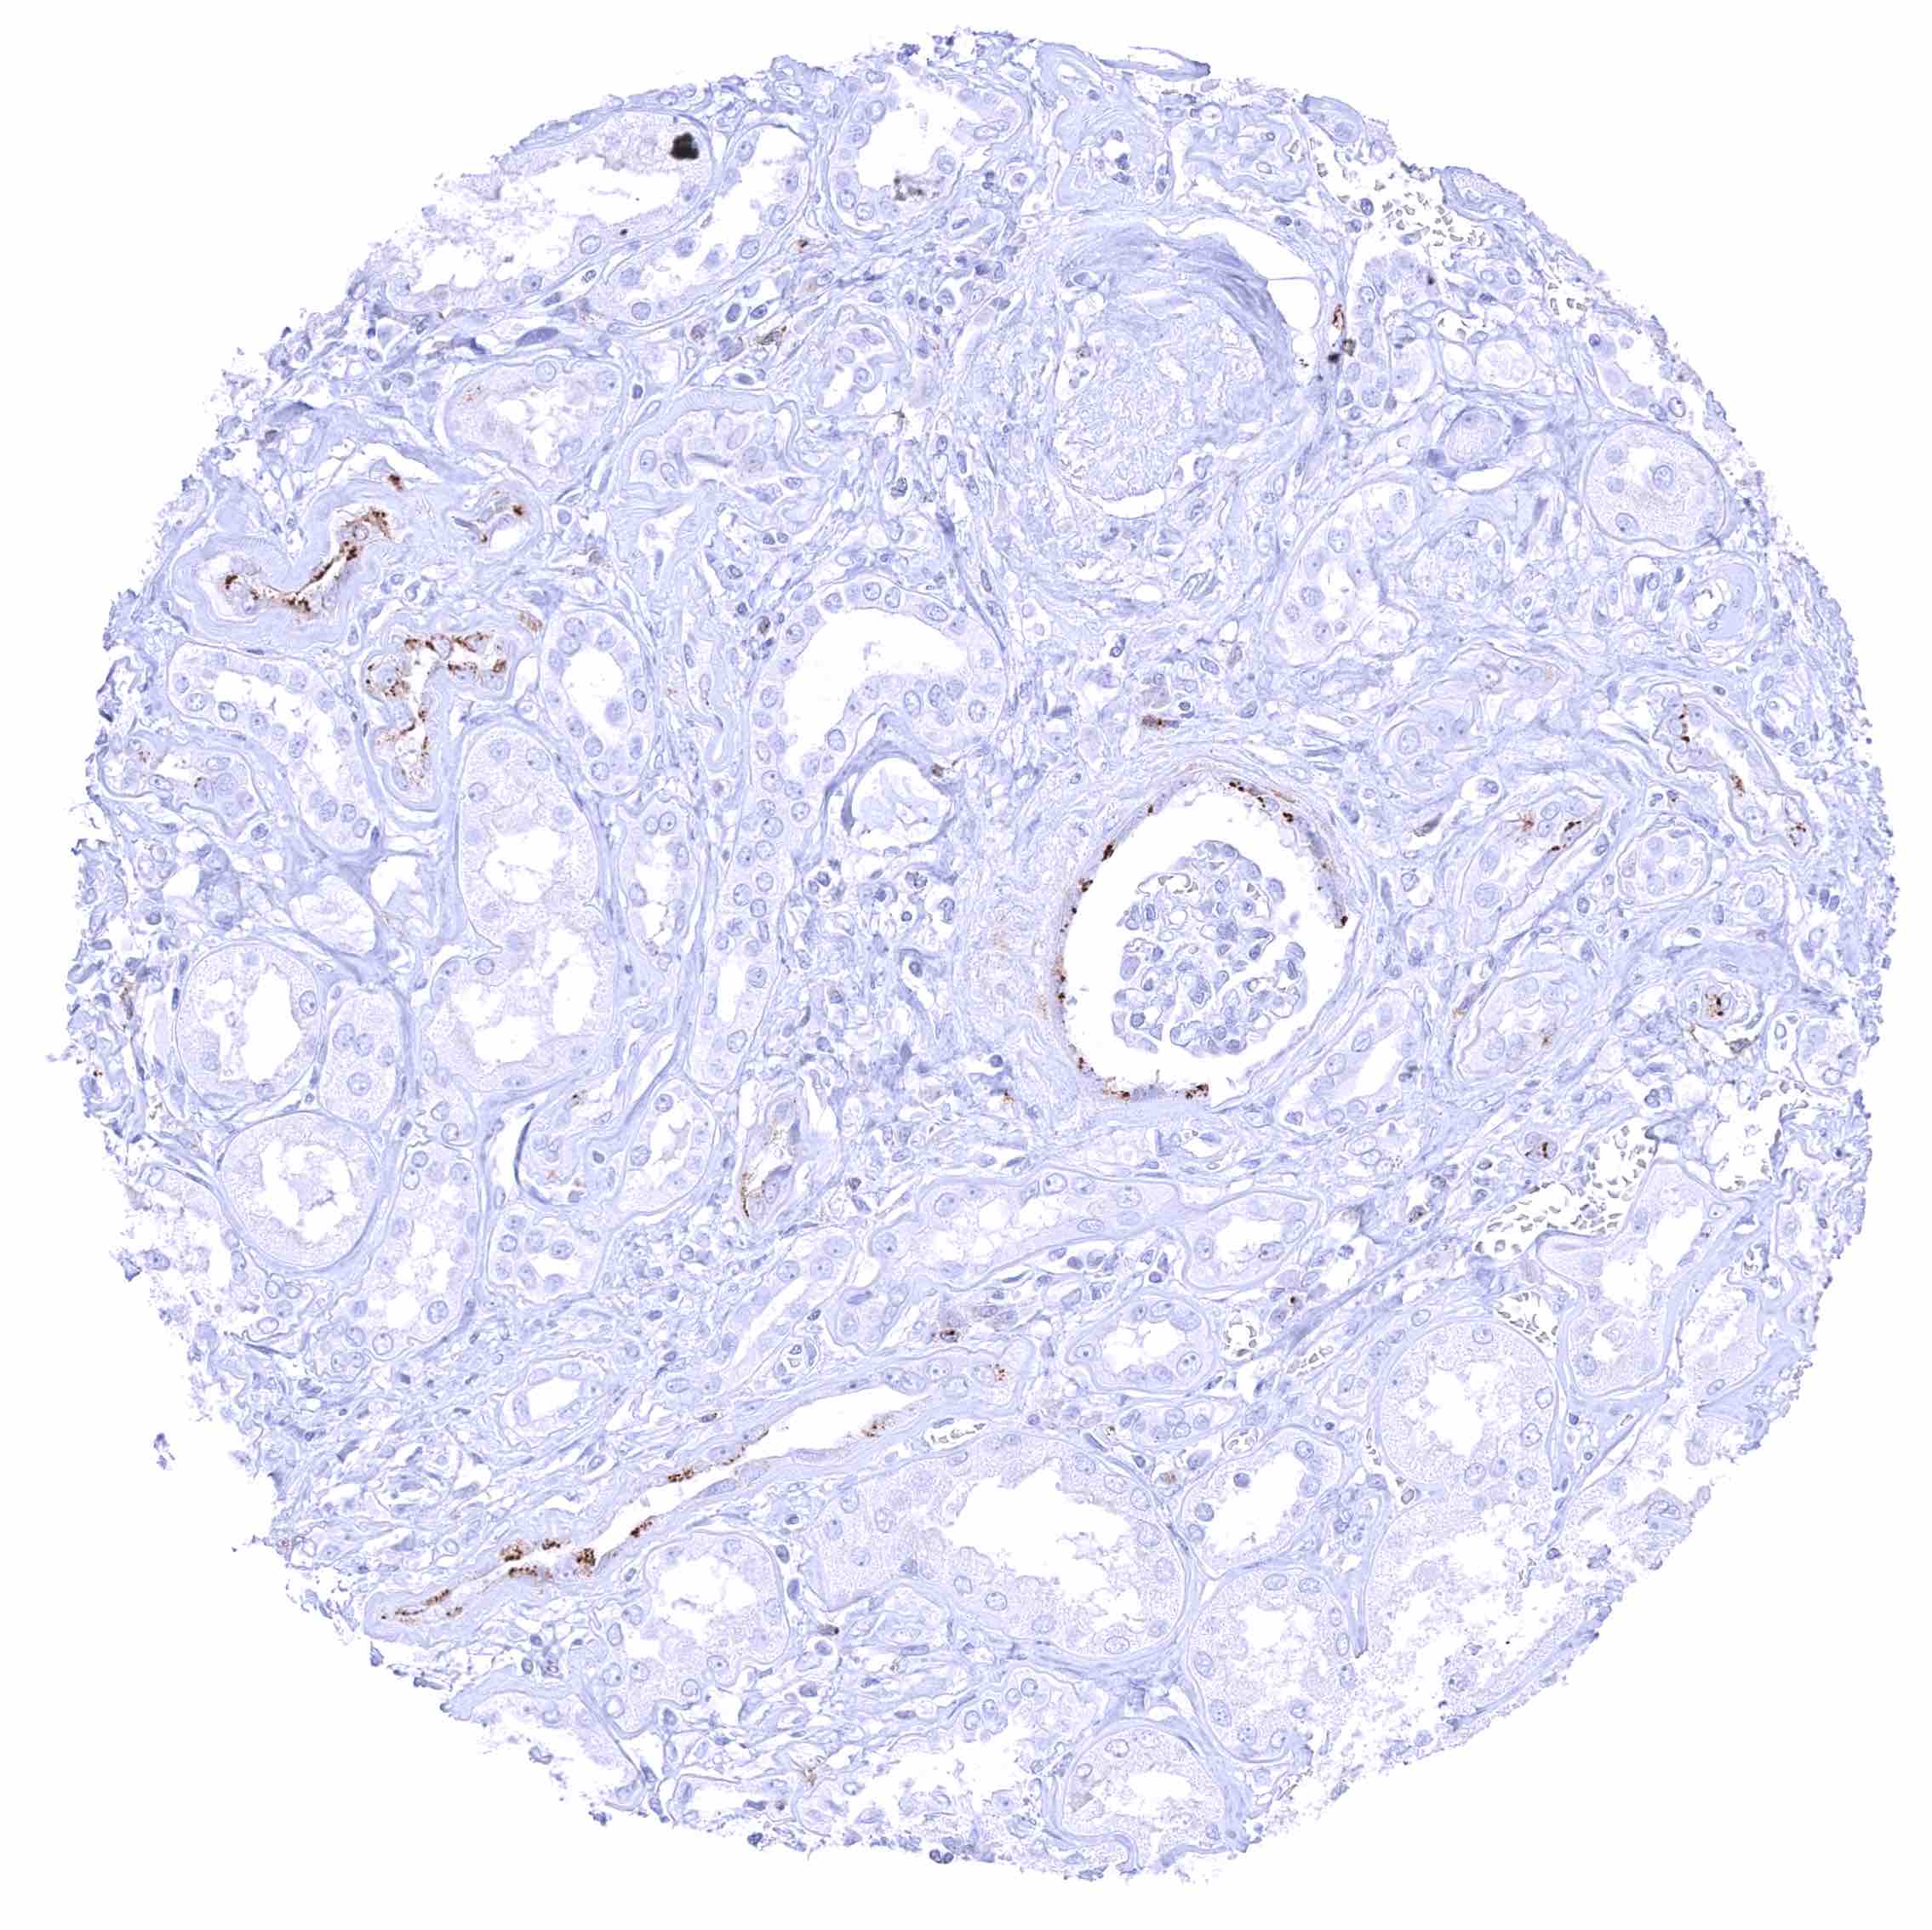

| Genitourinary | Kidney | A distinct CD70 staining of the luminal surface membrane can be seen in individual tubuli and at the parietal layer of the Bowman capsule. It is possible, that these stainings only (or preferably) occur in case of tissue damage. |

CD70 expression is most commonly seen in different types of lymphoma and in clear cell renal cell carcinoma. Other cancer types have also been described to express CD70 at lower frequency.